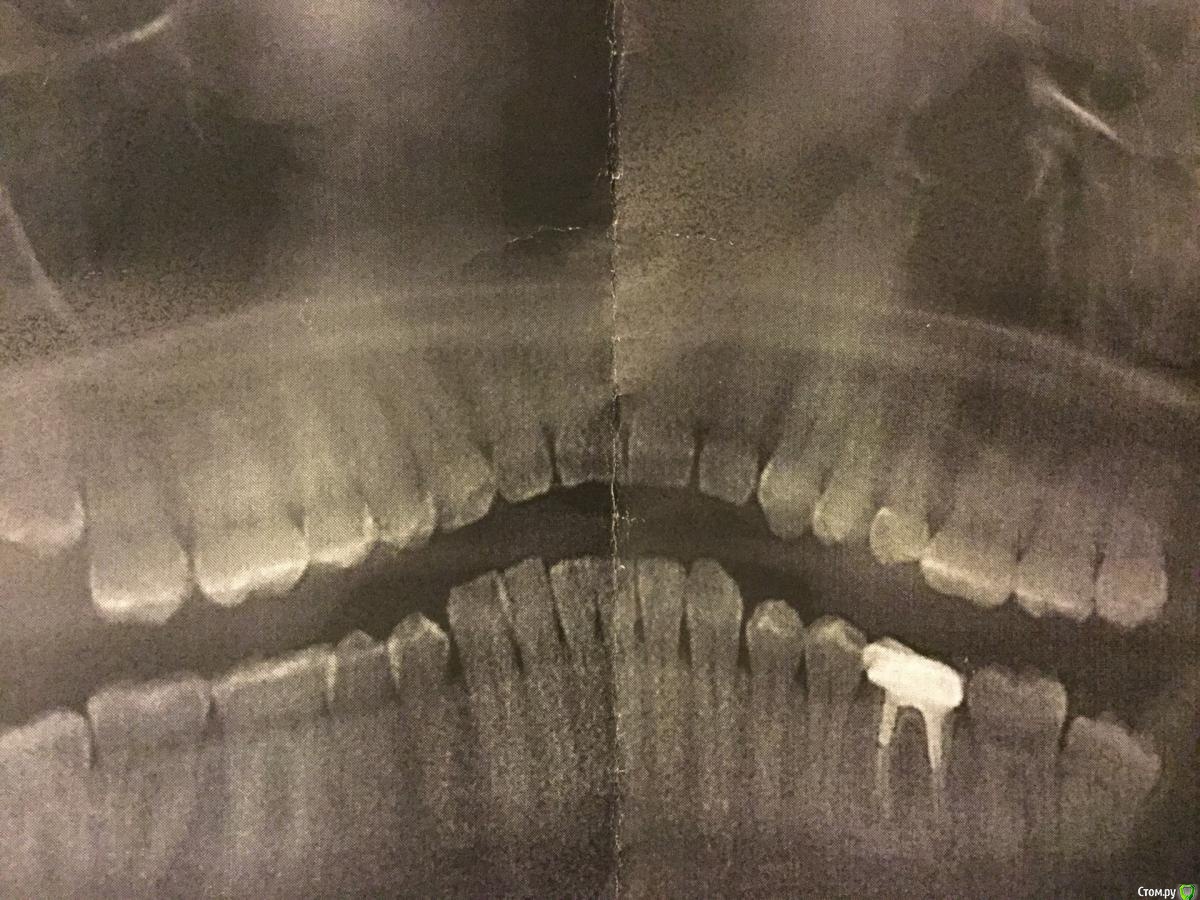

TR909 Опубликовано 19 декабря, 2018 Поделиться Опубликовано 19 декабря, 2018 Здравствуйте, Товарищи! Прошу помочь советом.Есть у меня многострадальный зуб, который лечили, потом перелечивали, потом пломбировали каналы, потом перепломбировывали, нахлобучили всю эту прелесть коронкой и я был абсолютно счастлив лет 7. Периодически распухала десна и даже как-то шел гной, но это всю фигня в масштабах вселенной, думал я. И вот опять десна распухла, а потом и часть челюсти толи онемела, толи как-будто там что-то чужеродное стало ощущаться и я, не долго думая, пошел к хорошему хирургу, сделали 3д рентген и обнаружили гной у корней моего многострадального зуба, причем вроде как немало гноя. Хороший хирург однозначно сказал, надо выдирать и ставить имплант (он не только хороший хирург, но и хороший имплантолог и вообще замечательный человек). А мне так жалко этот зубик с которым мы вместе так много прошли и вот сижу я и думаюю что с ним делать: попробовать еще раз вылечить или выдрать и забыть.Подсобите советом: лечит ли кто в Москве такие зубы, с запломбированными каналами, коронкой, гноем под корнями и свищом на десне и насколько вообще реально его вылечить? Или удалить нафиг и походить пока с дырой покопить деньги на имплант? Ссылка на комментарий

TR909 Опубликовано 19 декабря, 2018 Автор Поделиться Опубликовано 19 декабря, 2018 (изменено) Левая нижняя шестерка Изменено 19 декабря, 2018 пользователем TR909 Ссылка на комментарий

DmitrySH Опубликовано 19 декабря, 2018 Поделиться Опубликовано 19 декабря, 2018 Данный снимок невозможно интерпретировать в виду отсутствия четкости. Лучше всего переделать на визиографе 3 Ссылка на комментарий